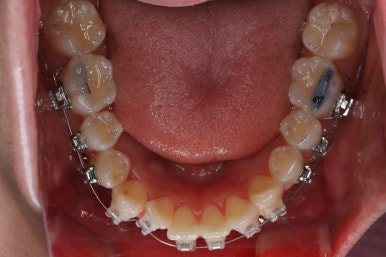

장치를 부착하였습니다.

이번에 부착한 장치는 엠파워 클리어라고 하는 자가결찰 세라믹장치 입니다.

세라믹이기 때문에 덜 보이며 자가결찰 장치이기 때문에 초기에 가지런해지는 속도가 빠르고 통증이 덜한 장점이 있습니다.

점점 가지런해지고 있습니다.

아래 앞니는 자리가 많이 부족했기 때문에 장치를 제대로 못 붙인 치아가 있고, 자리부터 확보해주고 있습니다.